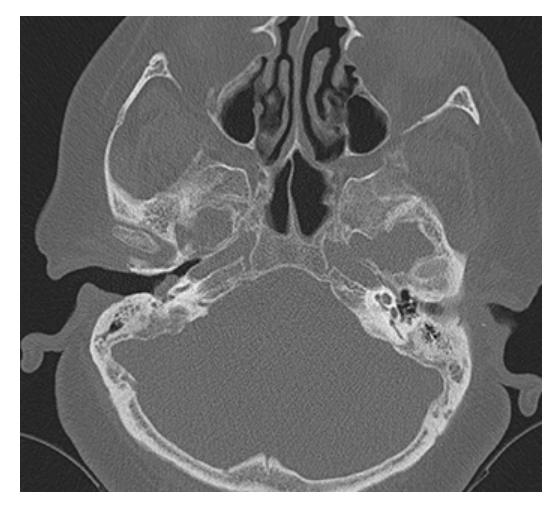

What does the figure show?

Cholesteatoma. Coronal NECT shows soft tissue density in the left middle ear with thickening of the tympanic membrane. The left scutum has a blunted appearance (compared to sharp tip of normal right side). Findings are consistent with a cholesteatoma.

What is A

Cholesteatoma. Axial NECT of the temporal bones shows soft tissue in the left middle ear located lateral to the ossicles in the epitympanum (Prussak space). Mastoidectomy has previously been performed on the right. Coronal CT

What is B

Cholesteatoma. Axial NECT in same patient shows soft tissue in left middle ear within Prussak space of the epitympanum with blunting of the scutum. Right mastoidectomy is present.